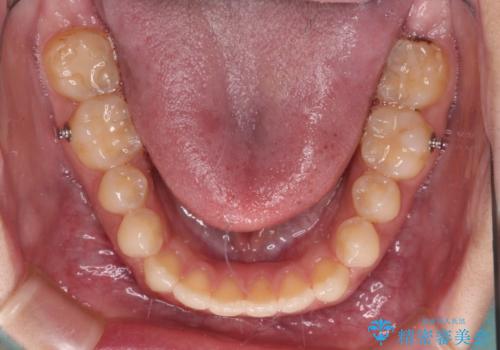

- インビザライン

- 1年10ヶ月

- 10-30回

仕上がりとしては、もう少し上下前歯を接触させたかったのですが、ここまで改善されたことで患者様は大変満足され、治療を終えることとなりました。